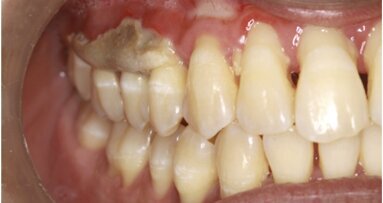

Algunas de la piezas presentan signos de anquilosis, por lo que se hace uso de ultrasonidos para facilitar las exodoncias (Figs. 2, 3). Se procede a la colocación de 6 implantes Frontier (GMI, IlerImplant, España) en las posiciones 16, 14, 12, 22, 24,y 26 (Figs. 4, 5).

El post-operatorio inmediato cursa de modo normal, pero a las 72 horas se empieza a observar una lesión a nivel de las piezas 12-13 (Fig. 6) con leve dolor a la palpación, así como exposición ósea. Al cabo de una semana se procede a la retirada de suturas, se observa que la lesión ha aumentado de tamaño (Fig. 7) y es entonces cuando se empieza con la terapia basada en ozono. Tomamos las copas de silicona de mayor diámetro para poder abarcar una mayor superficie de tratamiento y realizamos aplicaciones (Fig. 8) cada 48 horas de 3 ó 4 minutos de duración cada sesión.